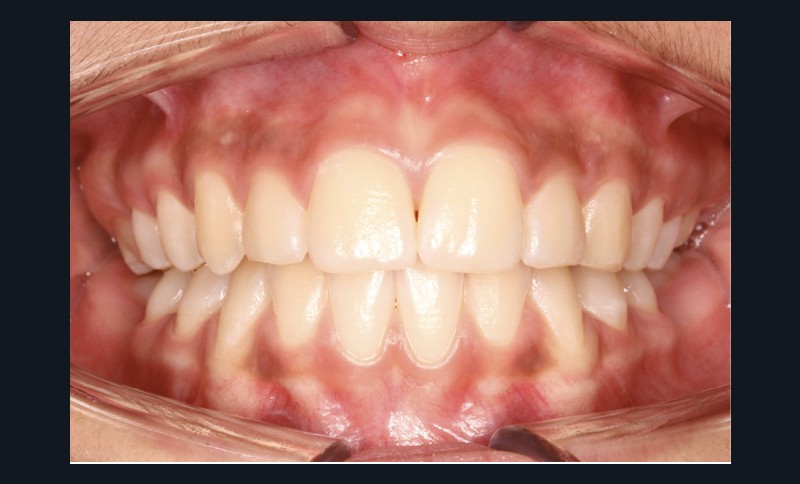

Examen endobuccal (fig. 2a-e)

L’hygiène est satisfaisante et le parodonte sain. On note aux deux arcades l’absence des premières molaires et la fermeture partielle des espaces d’extraction avec mésiorotation marquée de 17, 27 et 37. À la mandibule, l’encombrement antérieur est estimé à 2 mm et les espaces d’extraction résiduels à 12 mm.

Dans le sens transversal, malgré une occlusion correcte des secteurs latéraux, on observe une endoalvéolie maxillaire et une non-concordance des médianes incisives avec déviation de la médiane mandibulaire vers la droite. Le recouvrement incisif est normal.